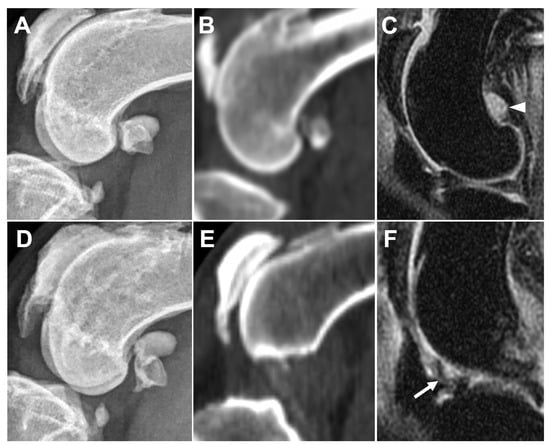

3.2.2. Ligament/Tendon Lesions

3.2.4. Subchondral Bone Lesions

3.2.5. Meniscal and Cartilage Lesions